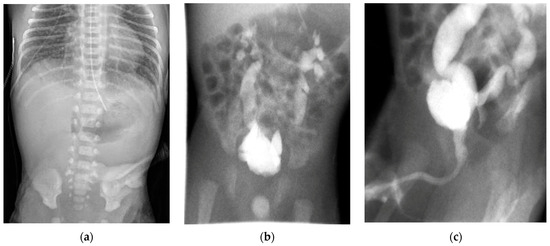

Figure 3.

Results of patient imaging including (a) an abdominal X-ray on day-of-life 2 confirming duodenal atresia with a double-bubble sign, a voiding cystourethrogram on day-of-life 16 with (b) anterior–posterior view with bilateral grade IV vesicoureteral reflux, and (c) a lateral view with a normal urethra considering the absence of a dilated posterior urethra.